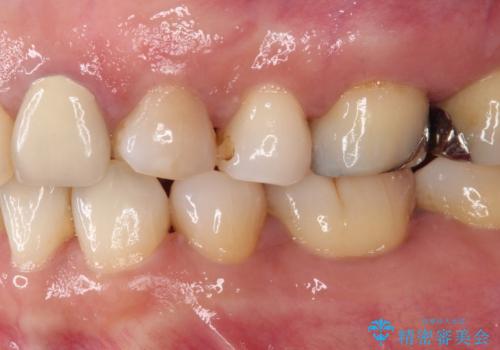

食事の度に痛む 根管治療とオールセラミッククラウン

- 食事の度に痛みを感じるとのことで来院された患者様です。

診査の結果、既に歯の神経は失活していたおり、叩いたり触ったりしたときの痛みも確認されました。

まずは根管治療を行い、その後にオールセラミッククラウンにて補綴することとしました。